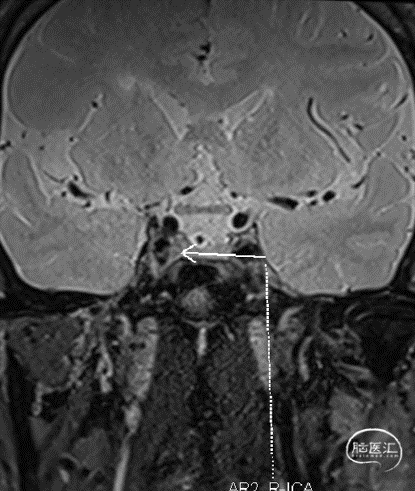

斑块分析:左侧大脑中动脉近中段M1段重度狭窄、M1远段-M2分支起始处混合斑块形成,局部管腔闭塞;远端分支较对侧明显减少。

T2

T1增强

颅脑灌注:左侧部分颞叶、额叶、枕叶及基底节区灌注较对侧减低、延迟。

左椎造影:左侧颈内动脉走形尚可,C4-C7段管壁欠光滑,C4段管腔轻度狭窄,约25%;C6段管腔轻度狭窄,约45%;左侧大脑前动脉走形尚可,A1-A2段管壁欠光滑;左侧大脑中动脉走形尚可,管壁欠光滑,M1段管腔重度狭窄,约90%,长约10mm,不除外夹层可能;左侧大脑前动脉通过软脑膜向右侧大脑中动脉供血区代偿供血,代偿分级2级。

左颈造影:左侧颈内动脉走形尚可,C4-C7段管壁欠光滑,C4段管腔轻度狭窄,约25%;C6段管腔轻度狭窄,约45%;左侧大脑前动脉走形尚可,A1-A2段管壁欠光滑;左侧大脑中动脉走形尚可,管壁欠光滑,M1段管腔重度狭窄,约90%,长约10mm,不除外夹层可能;左侧大脑前动脉通过软脑膜向右侧大脑中动脉供血区代偿供血,代偿分级2级。

2、DSA:左侧大脑中动脉M1段管腔重度狭窄,约90%,长约10mm,不除外夹层可能。

3、其他:斑块分析:左侧大脑中动脉近中段M1段重度狭窄、M1远段-M2分支起始处混合斑块形成,局部管腔闭塞;远端分支较对侧明显减少。颅脑灌注:左侧部分颞叶、额叶、枕叶及基底节区灌注较对侧减低、延迟。